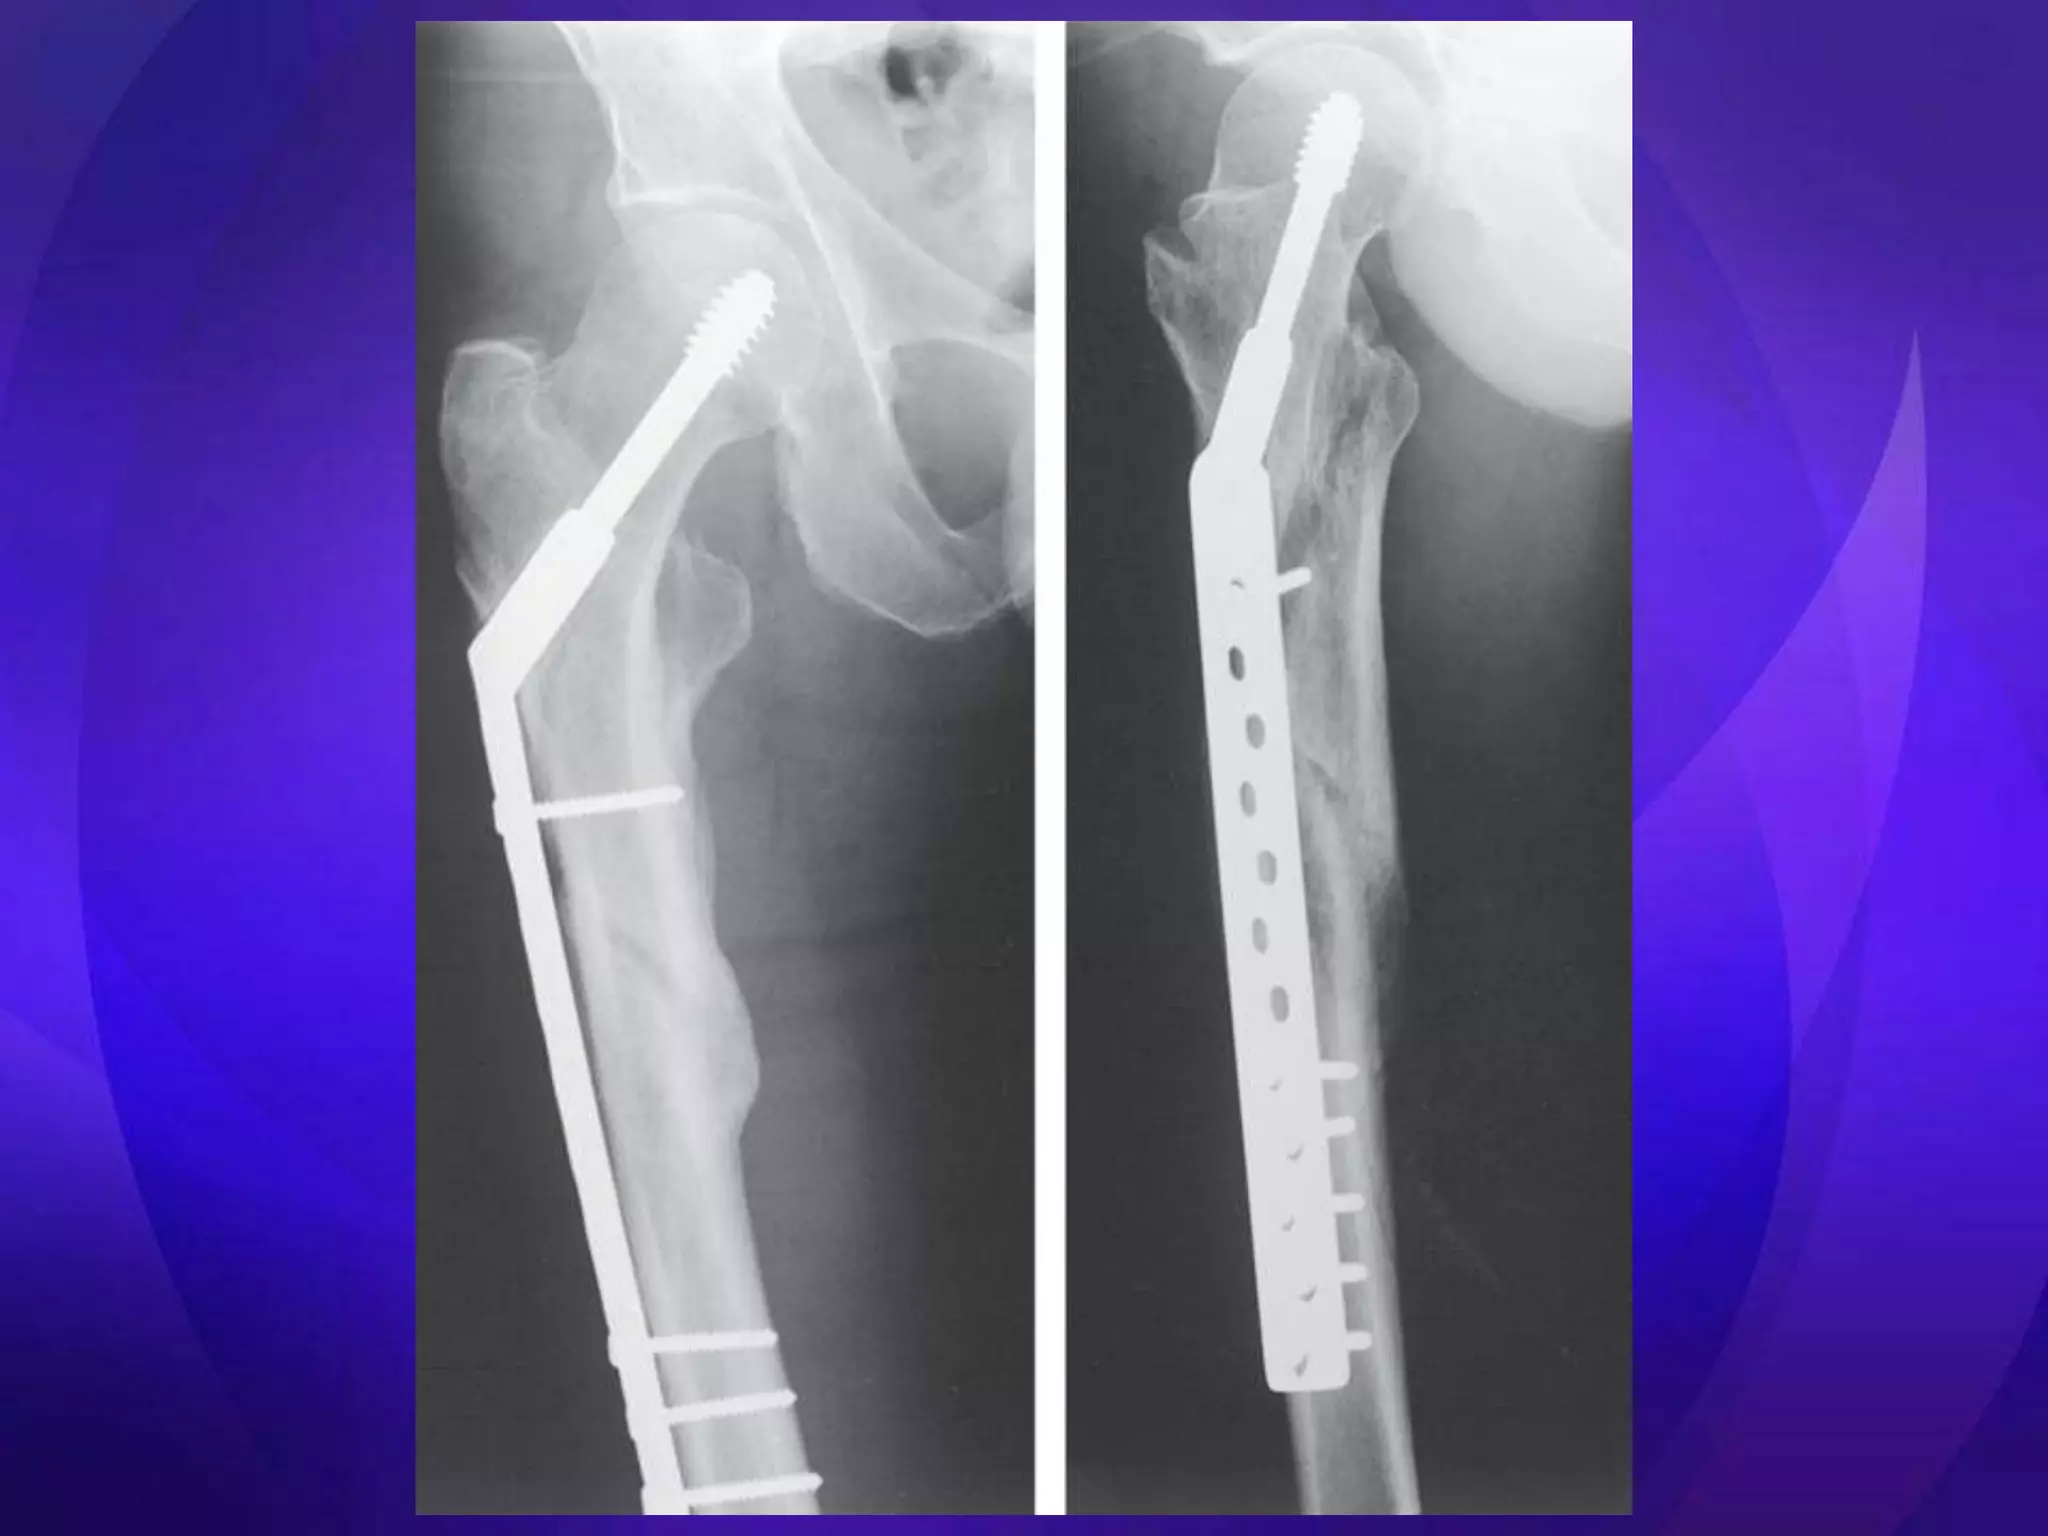

• Key issues – Medial cortical buttress – Reduction (esp varus deformity) • Extramedullary – ORIF – DHS, Medoff Sliding Plate, DCS, blade plate, locking plates • Intramedullary – Centromedullary – Cephalomedullary – Short vs long

• Resist axialloading better • Less stiff in torsion • Closed Rx • Short nails = femoral shaft – Preserve fracture biology fracture • Decreased moment arm • Femoral head screw cut on implant out • ? Autogenous grafting during reaming • Segmental/ pathological # • >97% union

• Tencer JOrth Res 1984 – Cadaveric study – Torsional stiffness better in plate devices – Axial loading better in locked IM nails – IM nail=3000N; plates=1000-1500N • Haynes Med Eng Phys 1997 – Cadaveric study – SGN=5761N; DHS=4660N(hard) 3225N(soft) • Aune Acta Orth Scan 1994 & Madsen J Ortho Res 1998 – Femoral shaft fractures with SGN • Parker & Handoll Cochrane Rev 2004, 2008, 2009 – Better intraoperative results and less fixation failures in cephalomedullary devices – Femoral shaft fractures with short nails